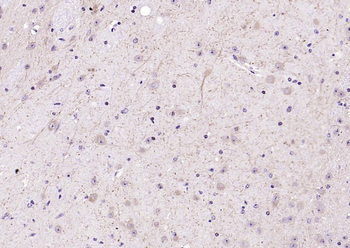

50 μl, 100 μl - KLF4 Recombinant Rabbit Monoclonal Antibody [orb608075]Featured

FC, ICC, IF, IHC-Fr, IHC-P, WB

Human, Mouse, Rat

Rat

Rabbit

Recombinant

Unconjugated

200 μl, 50 μl, 100 μl - Featured